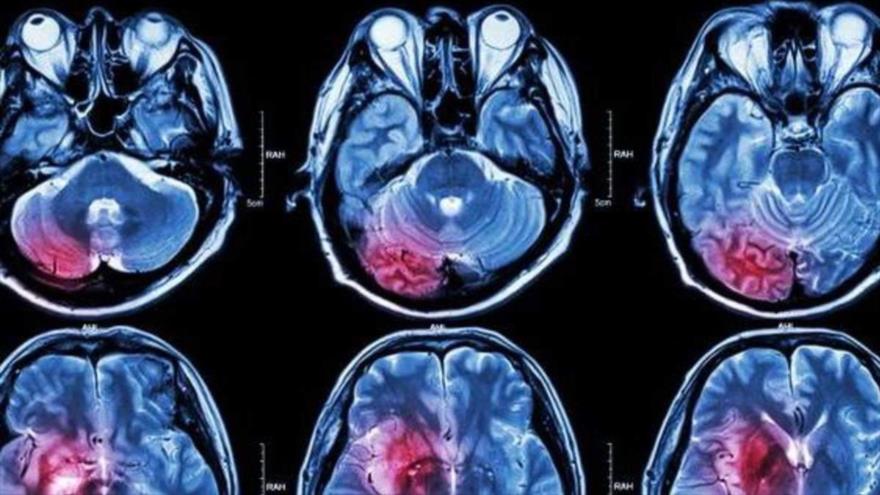

El estudio, realizado por la Universidad McGill (Canadá) y publicado recientemente en la revista Epidemiology, ha indicado que una mayor exposición a las partículas ultrafinas (UPF, por sus siglas en inglés) producidas por la quema de combustible, por ejemplo de los coches, podrían ser uno de los principales causantes del cáncer cerebral analizando los registros médicos y la exposición a la contaminación de 1,9 millones de canadienses adultos entre 1991 y 2016.

Los expertos identificaron 1400 tumores cerebrales durante el período de seguimiento. Cada aumento de 10 000/cm3 en las UFP se asoció con un aumento de la incidencia de este tipo de cáncer después de ajustar varios factores, como los sociodemográficos. Si esas personas además fumaban o tenían un alto índice de masa corporal, la prevalencia subía aún más. Las partículas PM2.5 y NO2 no se asociaron con una mayor incidencia de tumores cerebrales.